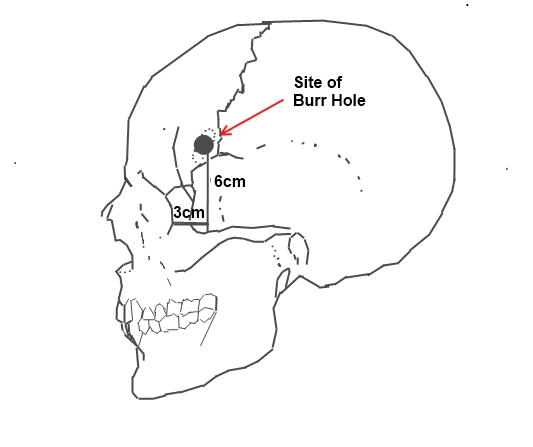

1935년 11월 12일, 리스본에 있는 산타 마르타 병원에서 모니즈는 정신 질환 치료를 위한 최초의 근대적 수술을 시행했다.[156] 환자는 병원 소속 정신병원에서 제공받았으며, 수술은 모니즈의 동료인 페드루 알메이다 리마가 마취하여 진행했다.[157][158] 리마는 환자의 두개골 측면에 천공을 낸 후, 피질하 백질 전전두엽 부위에 에탄올을 주입하여 연결 섬유 또는 연합 섬유를 파괴했다.[42] 이를 통해 주 뇌와 전두엽 피질과의 연결을 제거하여 모니즈가 "전두엽 장벽"이라고 부른 것을 만들었다.[42]모니즈는 이 첫 수술이 성공적이라고 판단했으며, 환자의 우울증이 감소했다고 발표했다. 그러나 환자는 실제로 정신병원에서 퇴원하지 못했다. 모니즈와 리마는 이후 7명의 환자들에게 에탄올 주입법을 사용했다. 그들은 아홉 번째 환자에게 이 수술을 전두엽 절제술(Leucotome)이라고 소개했고, 이전과는 달리 길이 11cm, 두께 2cm의 Cannula 관을 전두엽 앞에 심어 에탄올을 넣는 방법을 사용했다. 그들은 환자를 수술하던 도중 두뇌골을 자르는 것에 대한 위험성을 알아차렸을 것이다.